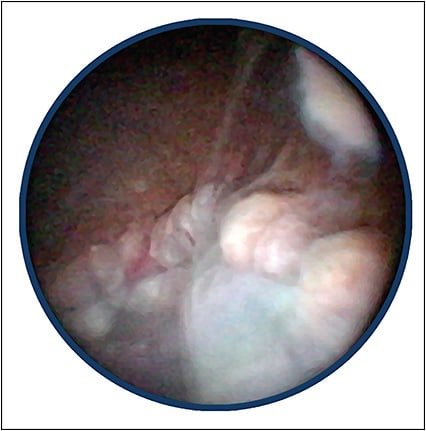

The purpose and goal of vitrectomy in the setting of endophthalmitis are to mitigate the inflammatory and infectious damage by debulking purulent material within the eye. I have performed a number of traditional vitrectomy procedures, which are very challenging due to a compromised anterior chamber, often with reduced corneal clarity that results in limited visualization of the posterior segment.

In most cases of vitrectomy utilizing a wide-angle visualization system only, the limited view of the posterior segment prevents a thorough vitrectomy. Most surgeons perform sufficient vitrectomy to enable visualization of the posterior pole, leaving behind a significant amount of anterior vitreous. This residual vitreous is nearly always opacified from purulent material and prevents a thorough examination of the peripheral retina for tears. The residual vitreous also serves as a scaffold for future membrane formation, leading to retinal and ciliary body traction.

Endoscopic vitrectomy dramatically improves the ability to perform a thorough removal of vitreous and residual debris. Endoscopy provides increased capacity to see not only posterior-segment structures that are normally visible with wide-angle visualization systems but also the pars plana, ciliary body, and anterior vitreous base with membrane formation, where vitreous opacification is the most significant.